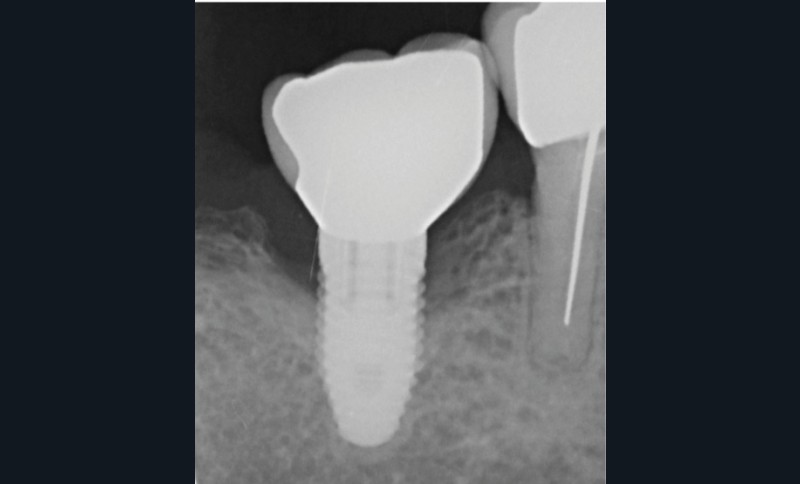

- Péri-implantite sur l’implant 47, diagnostiquée en août 2022

- Implant posé en 2017

- Nobel Replace Select RP (4,1 x 10 mm)